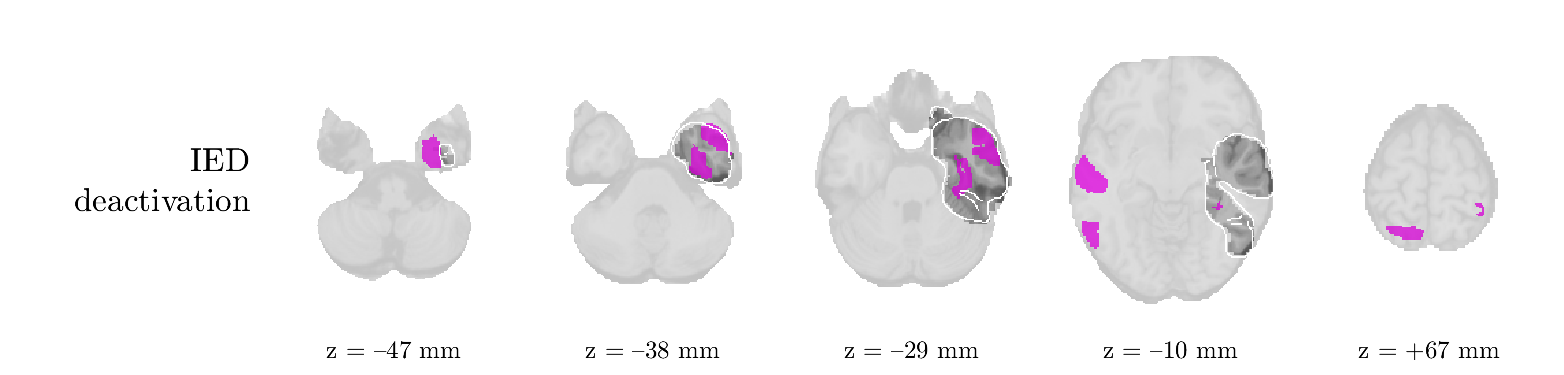

We analyze the solution with sources. Figure 1 shows the EEG signatures and HRF waveforms. One of the sources is highly correlated to the MWF reference (in grey), which was already known from Table B.3. This IED-related source had a typical low-frequency spectrum, which is expected for the typical spike-and-wave interictal discharges. The topography is relatively diffuse, although the highest amplitudes are mostly in the left hemisphere. This is in accordance with the lateralization of ictal onset zone (left temporal lobe, cfr. Table 1). There are some noteworthy observations to be made about some of the other components. The fourth has an unusually sharp spectrum, is mainly localized on two nonadjacent center electrodes, and is sustained for a single period of many seconds Hence, this component likely captured an artifact (of yet unknown origin), although we spotted no large-amplitude changes in the EEG itself. Similarly, the third source is only present at one frontal electrode, and exists in a frequency range above 20 Hz. It might represent a muscle artifact, e.g., due to frowning or twitching of some muscles in the forehead. The HRFs of all ROIs are shown in Figure 1(b). Two of the basis functions seem to have converged to a very similar waveform, which is an unfortunate possibility if two initial HRFs are too close to the same local optimum in their respective parameters. This reduces the expressive power of the basis set, which is clearly visible, since many ROIs have a nearly identical HRF. One of the twenty ROIs with the highest-entropy HRF overlapped the IOZ, although clearly this HRF (bold line) is not among the most dissimilar waveforms for this patient. This is also visible in Figure 2: both the HRF entropy and extremity maps show a small overlap with the delineated IOZ. Despite the good correspondence in the EEG domain, no significant (de)activation of the IED-component is found inside the IOZ.

We analyze the solution with sources, and show the results in Figure 3 and 4. As for patient 1, we found a source which is strongly correlated to the MWF envelope, and which had a mostly low-frequency behavior characteristic for spikes. The topography is mostly uninformative, and does not clearly correspond to the patient’s clinical data. The third source is mostly present at both sides of the head, is very sparsely active in time, and has a high-frequency content: this is most likely an artifact due to the neck muscles. Again, there is one of the highest-entropy HRFs which belongs to a ROI in the IOZ. Now, the waveform is clearly resolved from the other HRFs, through the strong initial dip (before 0 seconds). Such a dip is sometimes observed in HRFs, but its underlying physiological mechanism is not yet fully understood. It is possible that this dip reflects altered vascular autoregulation near the IOZ (cfr. the explanation in the Section 1 of the main text), or a rapid depletion in oxygen due to IED generation (before the IED becomes visible on the EEG). Figure 4 furthermore shows that the IED-related component is significantly active in parts of the IOZ, and deactive in others. As mentioned earlier, this deactivation may or may not be due to errors in sign correction. Interestingly, the ROI with the high alteration in neurovascular coupling is distinct from both the activated and deactivated ROIs.

We analyzed the solution with sources, and show the results in Figure 5 and 6. There is one source which is mostly correlated to the reference (but not extremely, see also Table B.3). This source had a right-temporal focus, conform the diagnosis in Table 1. The second source illustrates the phenomenon of an erroneous sign exchange between the spatial and spectral profiles. Also one of the HRFs has a negative polarity, which is a failure of the sign correction procedure (in this case, because there is exceptionally no positive overshoot). However, the HRF variability metrics are still interpretable, and indeed two ROIs among the ones with the highest-entropy HRFs overlap with the IOZ. The IED component is significantly active in a tiny portion of the IOZ (cfr. Figure 6). The second source is significantly active in symmetrical parts of the parietal lobe. Given its ongoing fluctuation over time, we hypothesize that this source captures a resting state network (RSN).

We analyze the solution with sources, and show the results in Figure 7 and 8. There is a clear IED-related component, with a very high correlation to the MWF reference, a typical spectrum, and an anterior-temporal focus, which corresponds very well to the patient’s diagnosis (cfr. Table 1). The fifth source seems present at only one channel, and has spectral harmonic at Hz and Hz. One of these peaks is reminiscent of the fourth component in patient 1. As Figure 8 shows, the HRF entropy and extremity prove to be strong biomarkers for the IOZ in this case, and also the significant IED activation and deactivation allow correct localization. In Figure 7, it is clear that some HRFs may still have the wrong sign, which means that the interpretation of ‘active’ and ‘deactivated’ is flipped in those ROIs. Hence, regions of significant deactivation are in fact significantly activated. The fourth source had a significant overlap with the auditory RSN, and its spectrum reveals activity in the band.

We analyze the solution with sources, and show the results in Figure 9 and 10. One source is strongly correlated to the MWF, while the other source is likely an artifact, given its very sparse temporal profile. Both sources coincide at one high-amplitude peak, by which we infer that this is probably an artifactual period in the signal. Indeed, when inspecting the original EEG signals, we found high-frequency muscle artifacts at these times. This source also had no significant activation in its spatial map, which corroborates its non-neuronal origin. The IED-related source had a broader spectrum than most other cases, and an uninformative topography. None of the ROIs with high-entropy HRFs is located in the IOZ. The pseudo t-map provides correct localization of the IOZ, however.

We analyze the solution with sources, and show the results in Figure 11 and 12. We found a clear IED-related component, with a characteristic spectrum and a topography which is backed up by the patient’s diagnosis (left anterior-temporal IOZ). The fourth source has a very similar topography and spectrum to the fifth source in patient 5. One HRF inside the IOZ had a high-entropy, and is distinguishable from the others by its very sluggish waveform, i.e., it is smeared out in time, with no sharp over- or undershoot. Also the pseudo t-map provided an accurate localization of the IOZ. Notably, in this patient, the extremity metric misses the deviating HRF in the IOZ (while the entropy metric picks it up). The second source overlapped with the frontal part of the default mode network (DMN), and is active in the and low bands.

We analyze the solution with sources, and show the results in Figure 13 and 14. We found two components which had correlated time courses. At the time of the peaks, we found higher-amplitude events in the EEG with dubious origin, hence they may or may not be artifacts. One of both components is more strongly correlated to the MWF, and its activation is concordant with the IOZ. The second component shows high overlap with the sensorimotor network. For this patient, none of the IOZ’s ROIs had extreme values of either HRF metric.

We analyze the solution with sources, and show the results in Figure 15 and 16. In this patient, there is only a moderate correlation of a component with the MWF reference time course. This component’s topography (left occipital) agrees with the clinical description, however. The HRF extremity (and not the entropy) is high in a small part of the IOZ. Both the significant IED activation and deactivation allow correct localization as well. The second source seemingly captured high-frequency oscillatory activity in the sensorimotor network, similar to the previous patient.

We analyze the solution with sources, and show the results in Figure 17 and 18. The IED-related source had a high correlation with the MWF reference, but an odd bimodal spectrum. Its EEG topography is very consistent with the clinical description. Both HRF extremity and entropy are useful biomarkers for the IOZ. The IED activation and deactivation maps each had a very small overlap with the IOZ. The second source is temporally sparse and captures high-frequency EEG variations, which we identified as muscle artifacts.

We analyze the solution with sources, and show the results in Figure 19 and 20. Again we observe an IED-related source and a seemingly artifactual source with a spectral peak near 34 Hz. Many of the high-entropy HRFs are highly noncausal, and are associated to ROIs inside the IOZ. Hence, with both HRF metrics, the highest-scoring ROIs provides good localization of the HRF. While there are no significantly active ROIs in the IOZ, there are several significantly deactivated ROIs, which may indicate that the sign standardization was not done flawlessly (cfr. also some of the negative-peaking HRFs for patient 10). Surprisingly, the second source had one significantly active ROI, which overlaps with the IOZ, but which did not match its EEG topography. Hence, the nature of this source remains ambiguous.